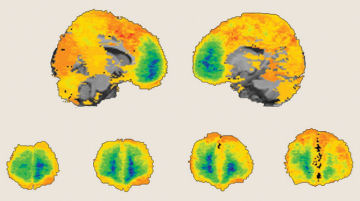

Psychiatrists classify PTSD as an anxiety disorder characterized by frequent re-experiencing of a traumatic event, emotional numbing, avoidance of reminders of the upsetting event, and excessive vigilance. Previous brain-imaging studies had suggested that PTSD involves overactivation of the amygdala, a structure that mediates fear responses, as a result of reduced activity in the ventromedial prefrontal cortex, an area that tamps down emotional reactions. The same studies also implicated deficient activity in the hippocampus, a memory-related structure, in PTSD. Still, it wasn’t clear whether these brain alterations caused PTSD or resulted from it.

Magnetic resonance imaging produced detailed images of participants’ brain structure.

Consistent with previous studies, Koenigs’ team found that none of the 15 vets with amygdala damage developed PTSD after their injury. PTSD emerged in only 7 of 40 vets with ventromedial prefrontal cortex damage, conflicting with earlier evidence that inactivity in this area promotes PTSD. The ventromedial prefrontal cortex apparently interacts with the amygdala in more complex ways than scientists have suspected, the researchers say.

Hippocampus damage showed no link to PTSD development in any group of combat vets.

“It appears that the amygdala and the ventromedial prefrontal cortex are necessary for PTSD to develop, whereas any hippocampus changes are probably responses to having PTSD,” says study coauthor Jordan Grafman, also of NINDS.